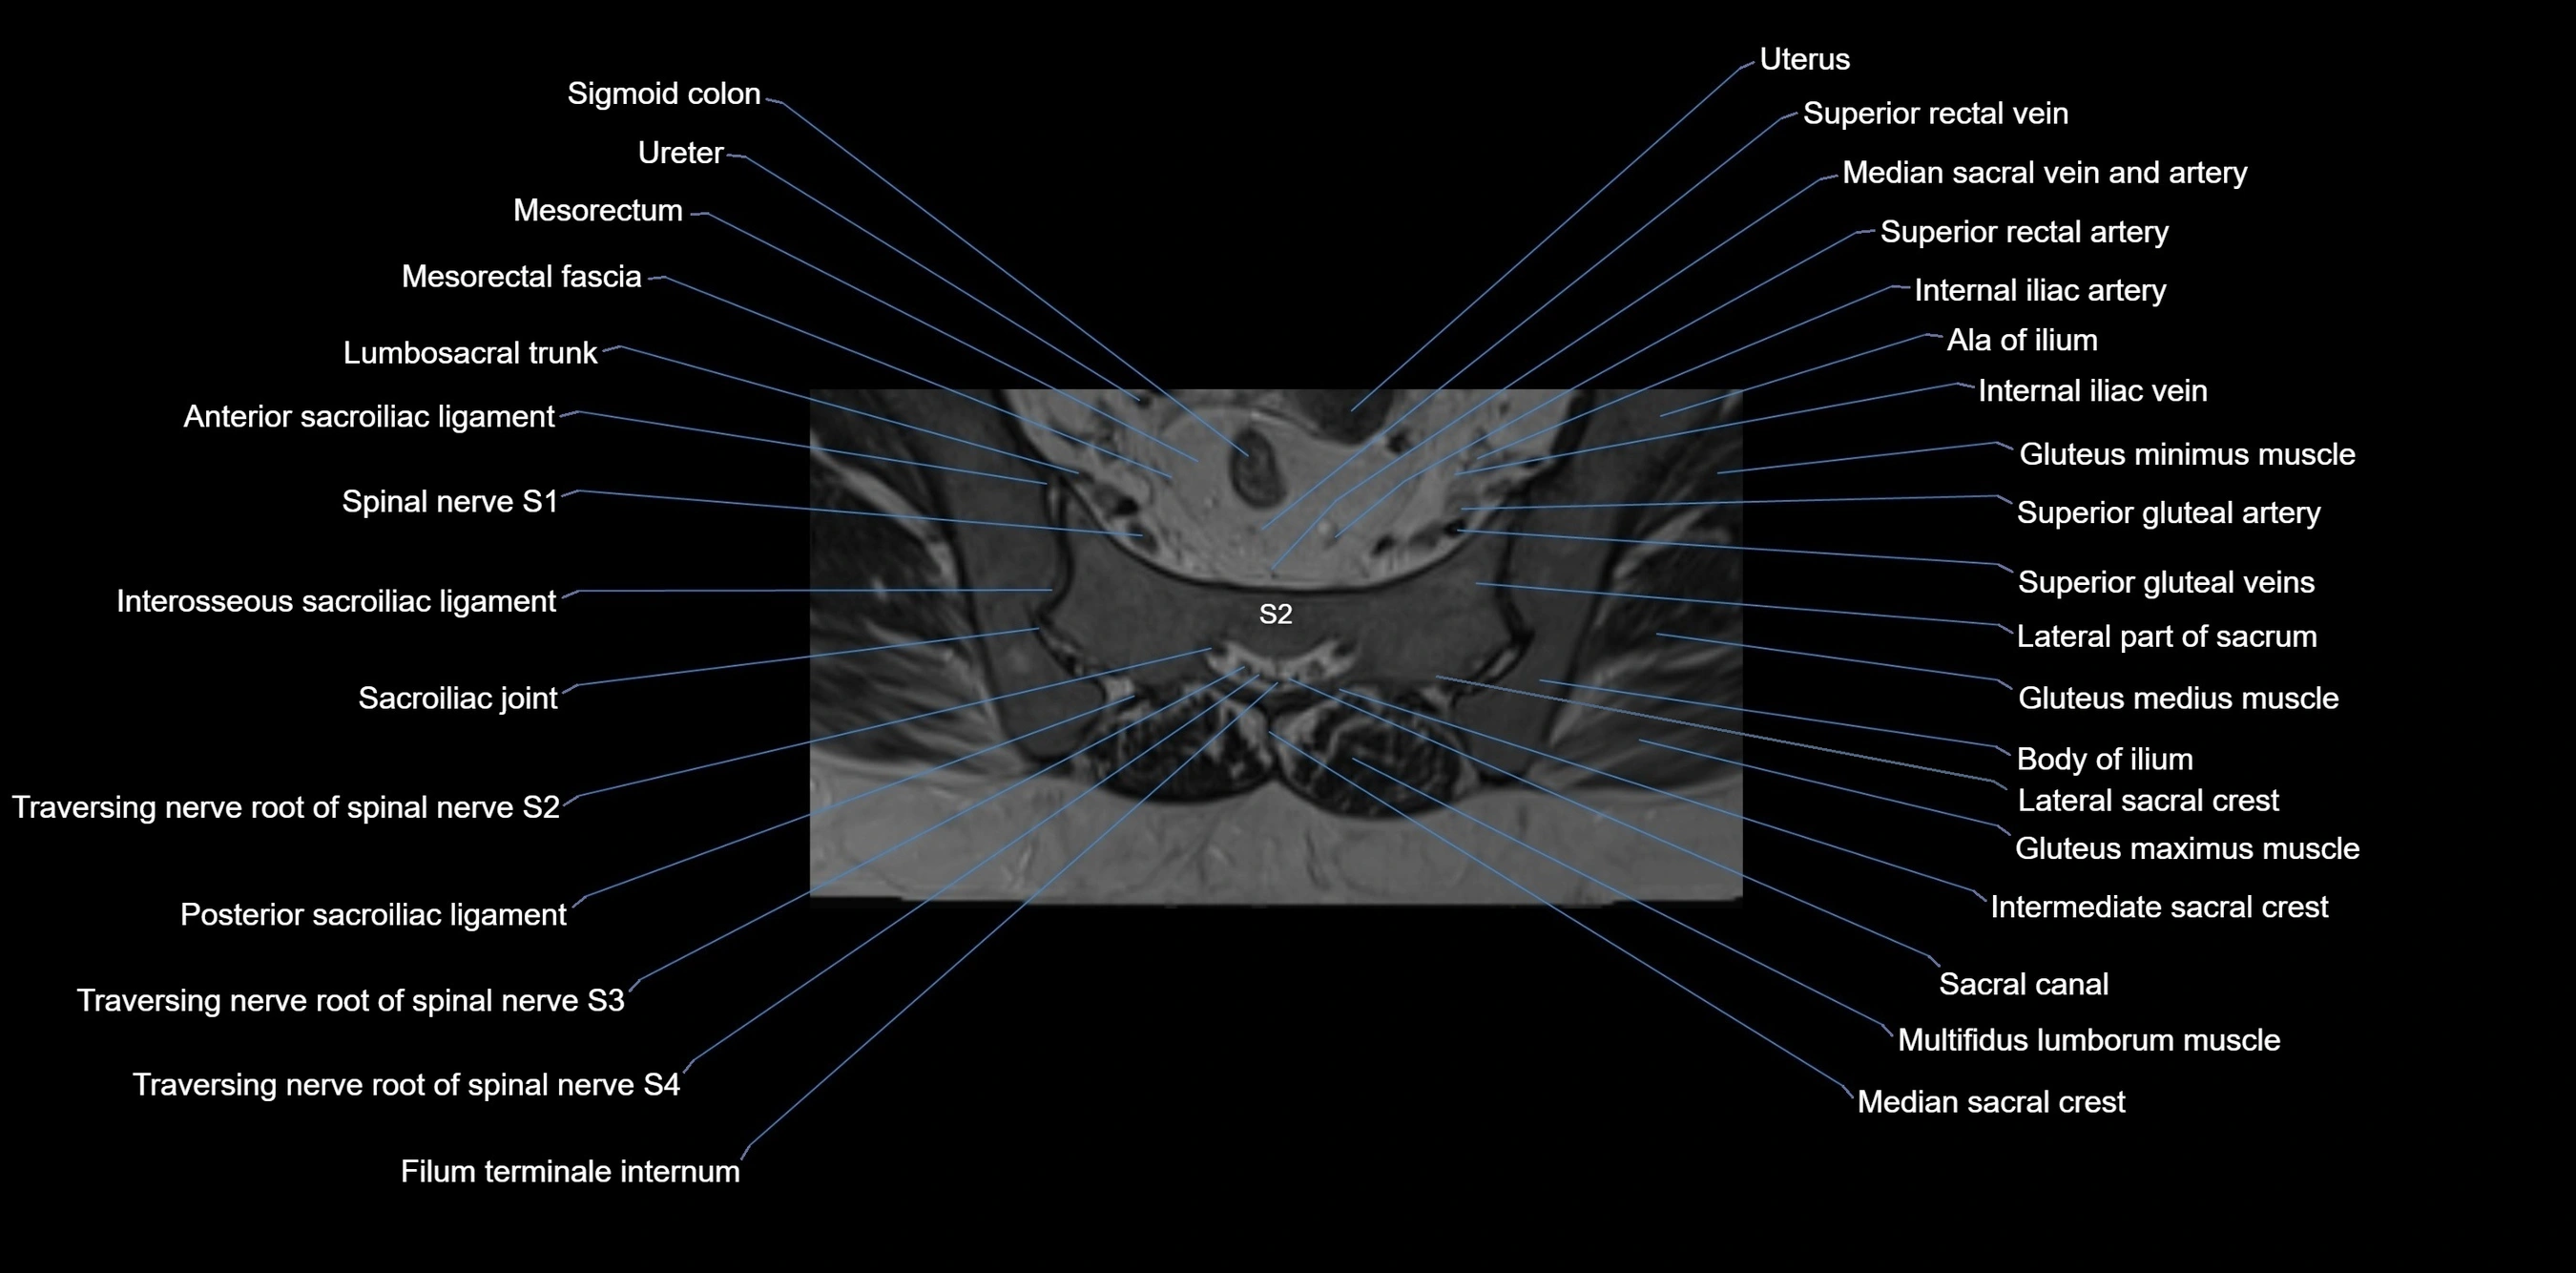

CT image

image